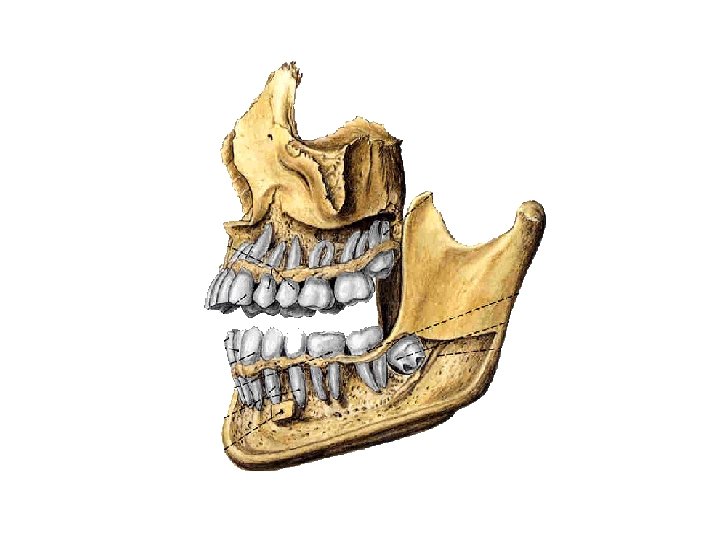

General description • Each tooth consists of 3 parts: – 牙冠Crown – 牙颈Neck – 牙根Root • 牙腔Dental cavity-contains connective tissue, blood vessels and nerves, and is continuous with the periodontal tissue through the root canal and apical foramen.

Calcified tissues 牙组织 • 牙质Dentine- is a yellowish white tissue, that forms the bulk of tooth. • 釉质Enamel -is a hard, brittle white tissue that covers the crown of the tooth • 牙骨质Cement -is an unusual form of bone that covers the root of the tooth • 牙髓 dental pulp 牙周组织Periodontal tissue • 牙周膜Periodontal membrane • 牙槽骨Alveolar bone • 牙龈Gum